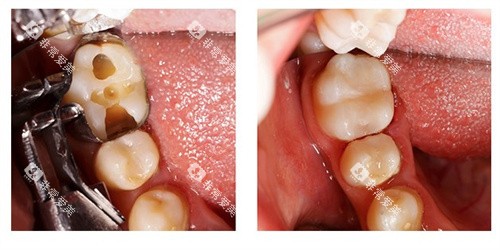

根管治疗主要用于治疗牙髓炎、根尖周炎等牙髓疾病。

其收费通常根据牙齿的部位和根管的数量来确定。

前牙的根管治疗相对简单,一般只有1 - 2个根管,收费在300 - 800元左右。

前磨牙通常有1 - 2个根管,费用在500 - 1000元左右。

磨牙的根管数量较多,一般有3 - 4个根管,治疗难度也相对较大,收费在800 - 1500元左右。

如果根管情况复杂,如根管钙化、弯曲等,治疗费用可能会更高。